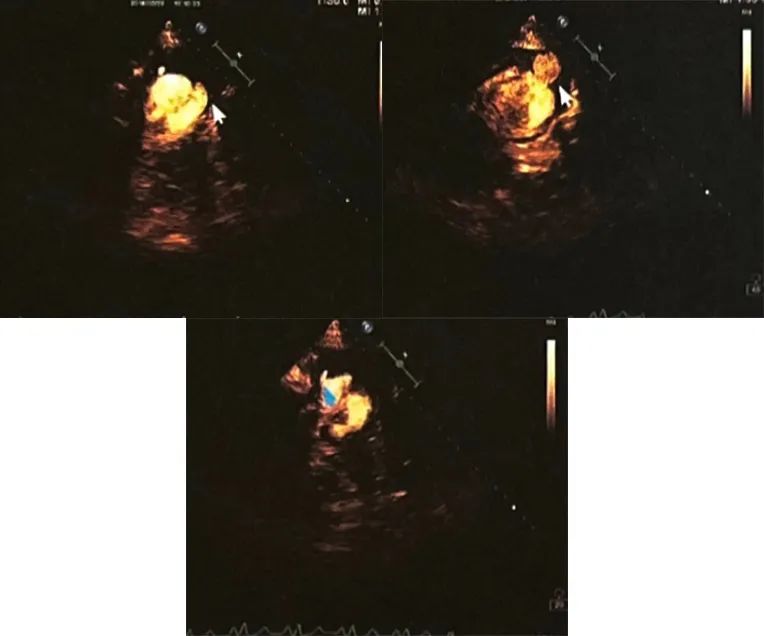

超声心动图示左心扩大,左心室节段性室壁运动异常,左心室心尖部真性室壁瘤形成,左心室心尖假性室壁瘤并血栓填充,升主动脉增宽,室间隔、左心室璧明显增厚,左心收缩功能减低,心包腔少量积液(LVEDD 6.3 cm,LVEF 38%)(图3)。

图3. 左心声学造影